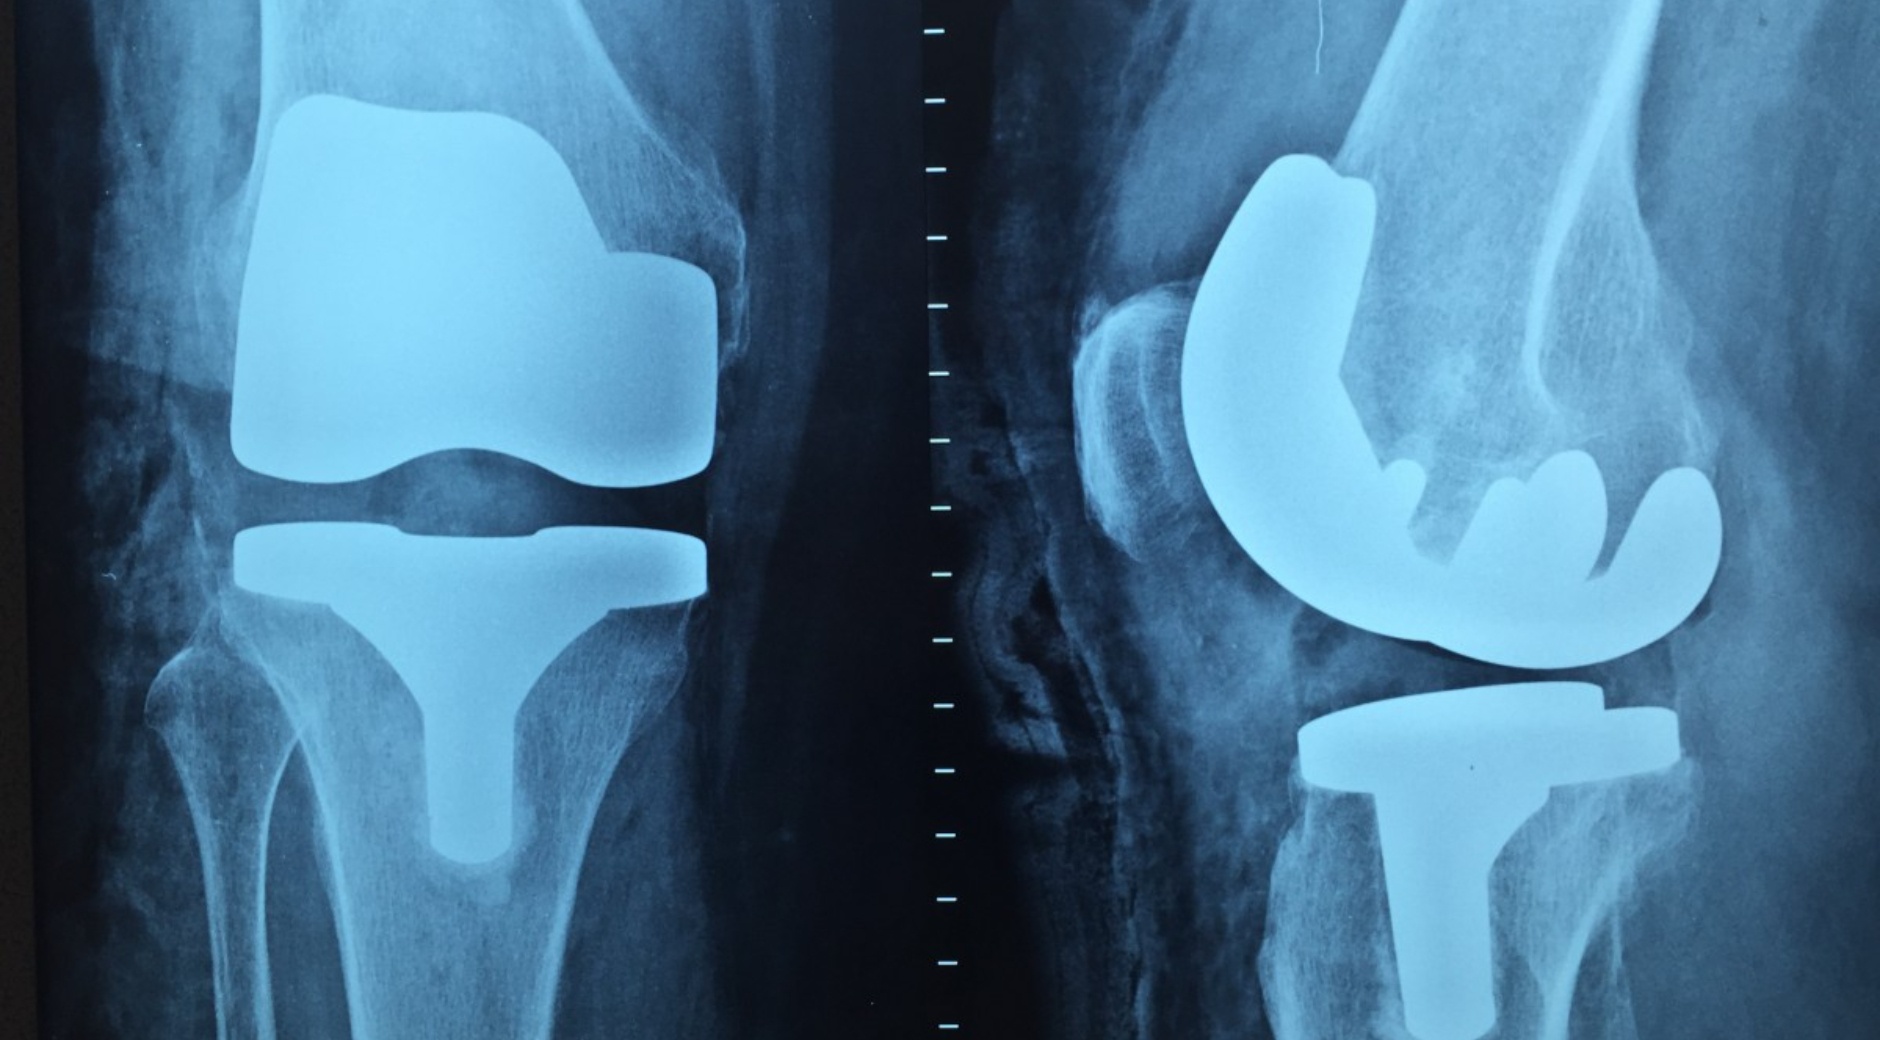

Такие симптомы говорят о нарушении кровотока и воспалении коленного сустава (артрит). Если заболевание длится достаточно долго, то возможно развитие дегенеративно-дистрофических изменений в суставе - артроз, - поясняет Елена Аверьянова, терапевт, кандидат медицинских наук, доцент ПсковГУ.